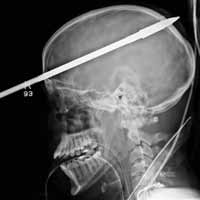

Một ca thoát chết hy hữu tại Bệnh viện Chợ Rẫy do nuốt kiếm. Ảnh: Thanh Huyền